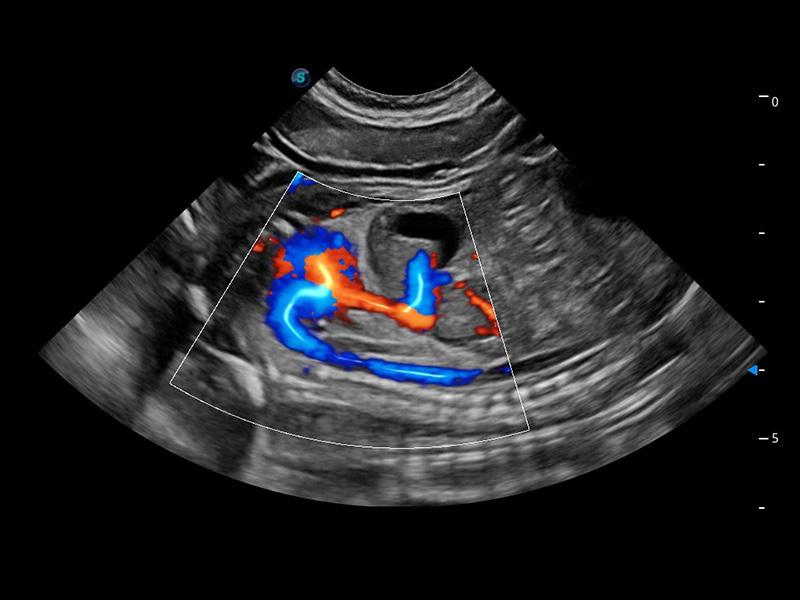

ProPet 60 作為一款高端臺式動物超聲設(shè)備,為動物醫(yī)生的日常診斷提供了一系列貼合動物臨床需求、解決臨床實際問題的高級成像功能。憑借全系列高清探頭,滿足醫(yī)生對腹部、心臟、生殖、淺表、肌骨等成像的所有需求,切實幫助您提升檢查效率,提高診斷信心。